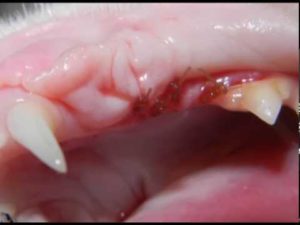

Feline Tooth Resorption

Posted on July 4, 2017